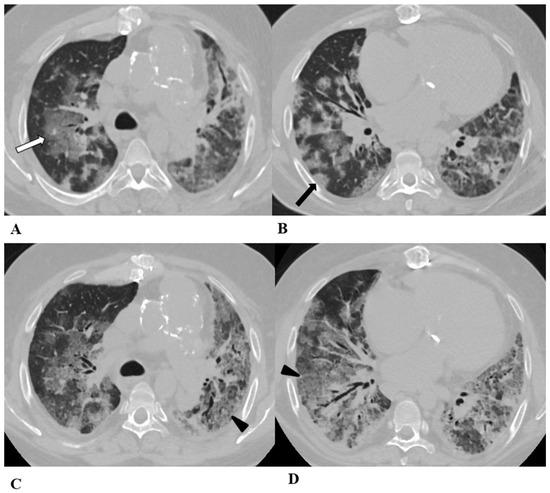

Figure 7.

Sarcoid-like reaction (SLR). A sarcoid-like reaction is a less-common non-pneumonitis irAE determined by the presence of non-caseating granulomatous inflammation in the lung parenchyma and lymph nodes, without criteria for systemic sarcoidosis [21].

Sarcoid-like reaction HRCT findings are represented in most cases by bilateral and symmetrical hilar and mediastinal lymphadenopathy, sometimes associated with peribronchovascular micronodules, peribronchial interstitial thickening and the infrequent coalescence of micronodules forming pseudo-masses with a predominantly dependent distribution. Lung parenchyma may be involved without adenopathy [11,13,22].

Bronchoalveolar lavage (BAL) shows moderate lymphocytic alveolitis, and its first-line treatment is with oral corticosteroids.

(A–D) A 75-year-old man with myelodysplasia and renal cell carcinoma. Fever, fatigue, cough and dyspnea affected the patient from the fifth month of treatment with pembrolizumab.

The axial chest CT image showed widespread micronodules with a miliary and perilymphatic distribution (A). Six days later, along with a moderate clinical worsening, the chest CT highlighted the development of large confluent areas in both lower lobes, with peripheral and declivous locations and the persistence of diffuse bilateral parenchymal micronodules (B); a mediastinal window of the same CT scan of image B demonstrated the volumetric enlargement of some lymphadenopathies in the sub-carinal station (white arrow (C)).

Chest CT performed 20 days later (D) after the discontinuation of pembrolizumab and treatment with oral steroids showed significant improvement in the pulmonary picture, with the complete resolution of the consolidations and a tendency towards the resolution of the bilateral parenchymal micronodulia.